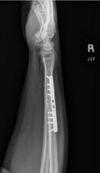

Which of the following is (are) typically associated with a Colles’ fracture?

C - 2 and 3 only

A Colles fracture usually is caused by a fall onto an outstretched (extended) hand to “brace” a fall. The wrist then suffers an impacted transverse fracture of the distal inch of the radius, most often with an accompanying chip fracture of the ulnar styloid process. Because of the hand position at the time of the fall, the fracture usually is displaced backward approximately 30 degrees. The proximal radius, the radial head, is not involved in this type fracture.